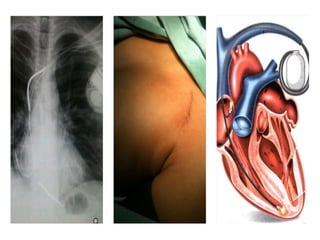

• Após a limpeza rigorosa da região peitoral do lado esquerdo ou direito,

o local abaixo da clavícula recebe anestesia local e é feita uma pequena

incisão. Em seguida, o eletrodo do marca passo é cuidadosamente

introduzido por uma veia até o coração. O médico monitora o

posicionamento correto do eletrodo no coração por meio de um sistema

de raios X.

• Depois de testar a posição e o funcionamento do eletrodo, ele é

conectado ao marcapasso, que é implantado em uma pequena “bolsa”

sob da pele. Para finalizar, o médico fecha o local da incisão.

COMO É O PROCEDIMENTO PARA COLOCAR O MARCA PASSO ?

PROCEDIMENTO DE IMPLANTE DE MARCA PASSO REALIZADO NA

SALA DE HEMODINÂMICA ( RADIOLOGIA INTERVENCIONISTA )